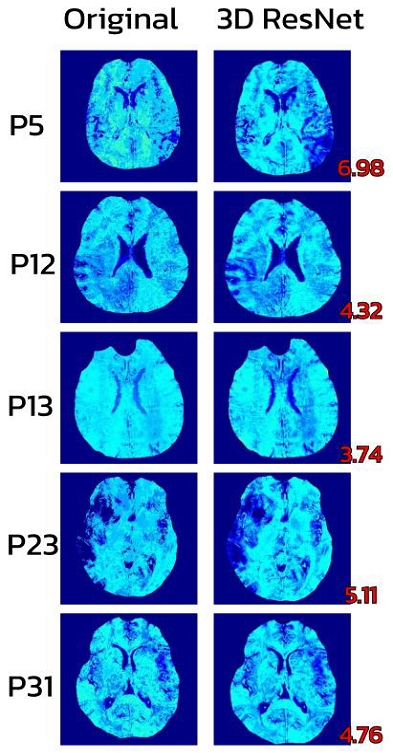

그림 3은 3D ResNet 모델이 예측한 산소추출률 값과 Ground Truth를 시각적으로 비교한 결과로, 네 명의 환자 모두에서 높은 일치도가 확인되었다. 평균 산소추출률 RMSE는 기존 3D CNN의 5.19에서 제안한 3D ResNet 모델의 4.98로 약 0.21 감소하였으며, 이는 약 4.0%의 성능 향상에 해당하여 3D ResNet 모델의 예측 우수성을 입증하였다.

또한 표 3에서는 동일한 코넬대학교 의과대학 데이터셋을 사용하여 기존 2D LSTM[5], 3D CNN[6], 그리고 본 연구에서 제안하는 3D ResNet 모델 간 산소추출률 평균 RMSE를 비교하였다. 데이터 분할 방식에 일부 차이가 있었음에도 불구하고, 제안된 3D ResNet 모델이 가장 낮은 RMSE를 달성하여 산소추출률 예측 정확도 측면에서 기존 방법들을 능가함을 보여주었다.